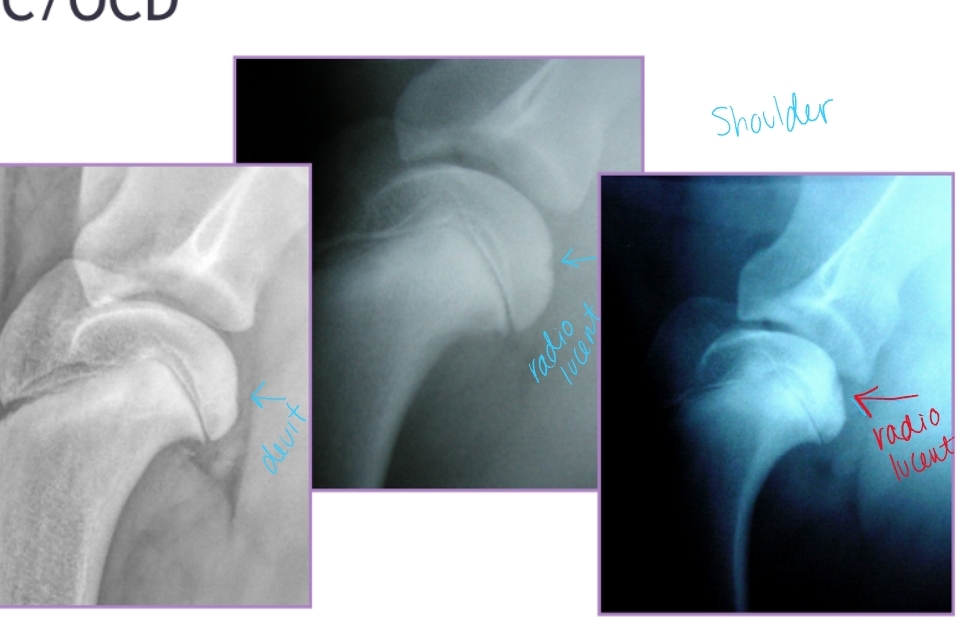

Osteochondrosis + Osteochondritis Dissecans

Et: Defect in normal endochondral ossification

Shoulder(most common), Elbow, Stifle, Hock

Path: Failure of cartilage to ossify → thickened cartilage (OC) → poor nutrition → mechanical trauma → cartilage fissuring/flap(OCD) → synovial inflammation → pain

Sig: Juvenile large breed dogs

Cs: Lameness, Pain, Decreased ROM, Muscle atrophy, Joint effusion palpable

Dt: Radiographs, CT

Caudal humeral head – lateral view

Medial humeral condyle – oblique view(elbow)

Medial aspect of lateral femoral condyle – AP view

Medial/lateral trochlear ridges of hock – AP/oblique views

Tx: Arthrotomy, arthroscopy, remove cartilage flap, debridement of subchondral bleeding bone

Px:

Shoulder: excellent

Elbow/Stifle: good

Hock: guarded

Osteochondrosis and Osteochondritis Dissecans

Et: Defect of normal endochondral ossification

Shoulder

Sig: large breed dogs, rapid growth, 5-10 months

Cs: lameness, pain, decreased ROM, muscle atrophy, effusion

Dt:

Rads: Divot of subchondral bone, OA, free cartilage flap

CT: Detects subtle subchondral bone lesions

Tx: Arthrotomy or arthroscopy

Remove cartilage flap, debride subchondral bone, promote fibrocartilage repair